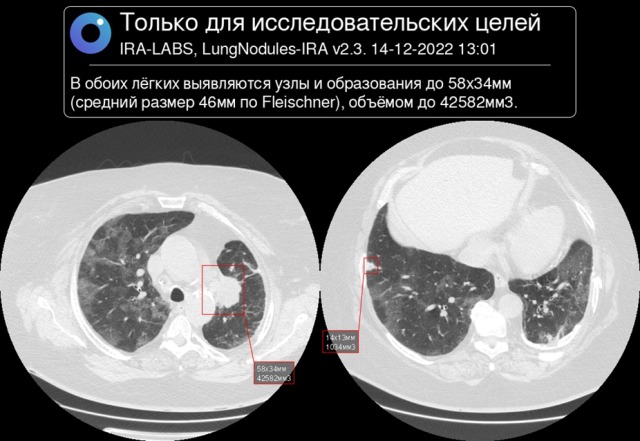

Для исследования специалисты использовали 10500 КТ-снимков. КТ-снимки органов грудной клетки деперсонализировались и направлялись на платформу IRA-LABS. Система осуществляла анализ полученных изображений: при обнаружении очаговых образований в легком указывалась их локализация, размер и объем, после чего снимки направлялись врачам-рентгенологам красноярского онкологического диспансера для анализа полученных результатов.

По результатам анализа полученных данных исследователи установили, что в 71% искусственный интеллект поставил верный диагноз и смог распознать рак легкого, в 140 случаях платформа распознала другие патологии легких, которые также были подтверждены врачами-рентгенологами.